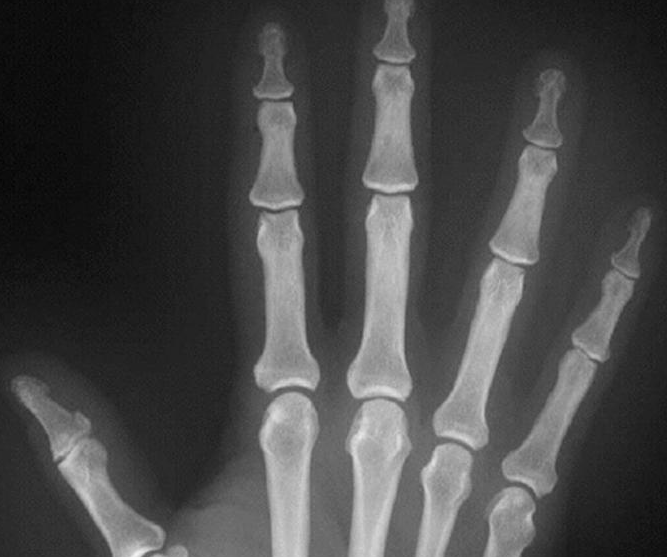

The initial radiographic bone shows a hook-like degradation of the metacarpal tip on the radial and palmar portion of their boundary in an anteroposterior projection. Plain X-rays typically demonstrate abnormalities and subluxations in individuals with Jaccoud Arthropathy.

” Hook” erosions can happen on the radial palmar side of the metacarpal heads. These erosions are different from the “margin” erosions that happen with rheumatoid arthritis.

Inflammation, obliteration of bone and cartilage, or degradation of articular surfaces are not symptoms of Jaccoud’s arthropathy. Most people with Jaccoud’s arthropathy do not have an abnormal ESR or rheumatoid factor test. Although the hands are most frequently affected, this illness has also been found to affect the feet.